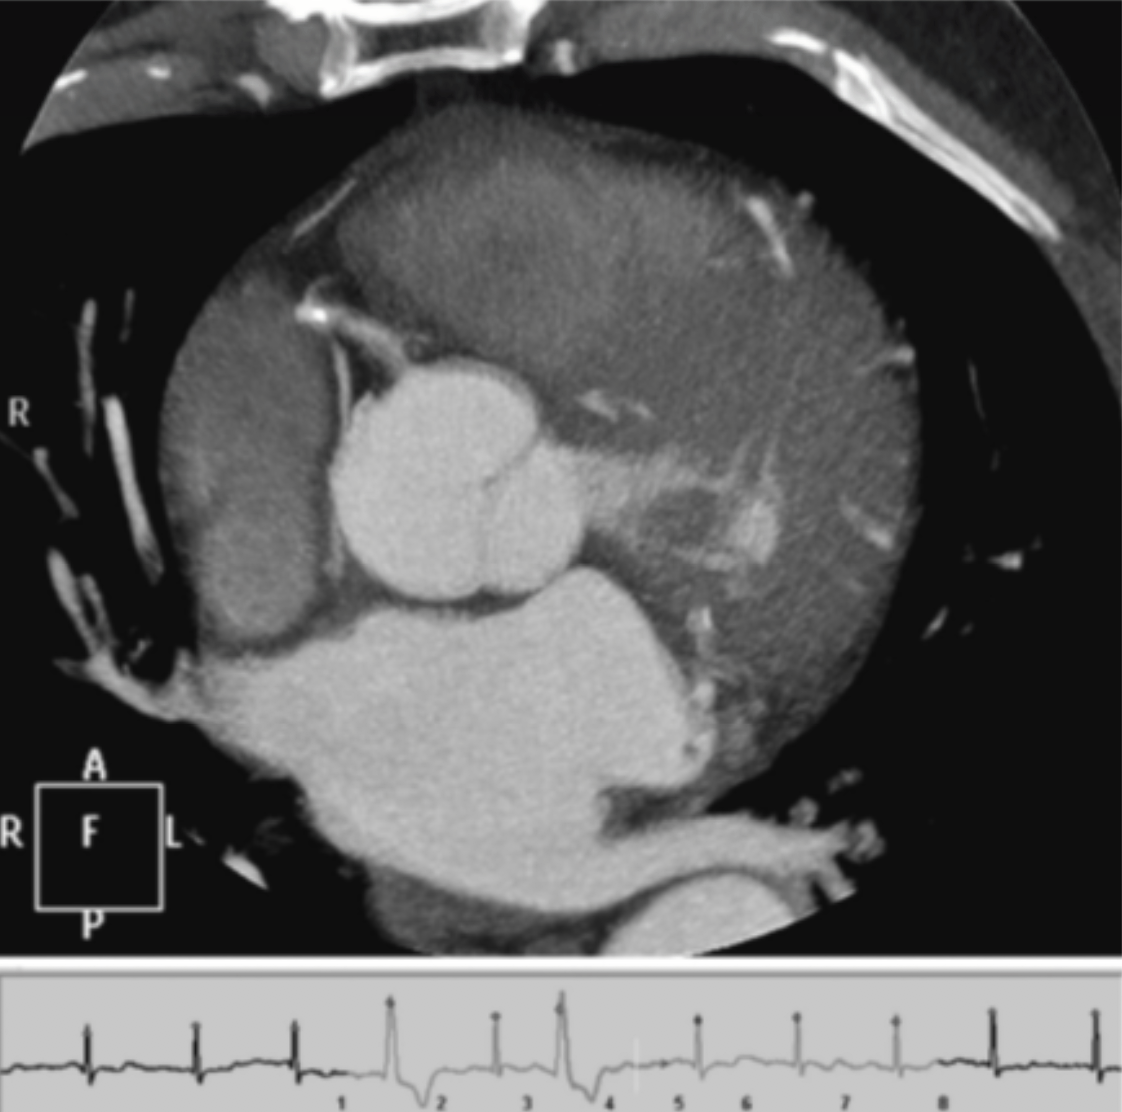

Based on the comparative appearance of these two images, what element of the reconstruction was modified during the second reconstruction?

Slice Thickness